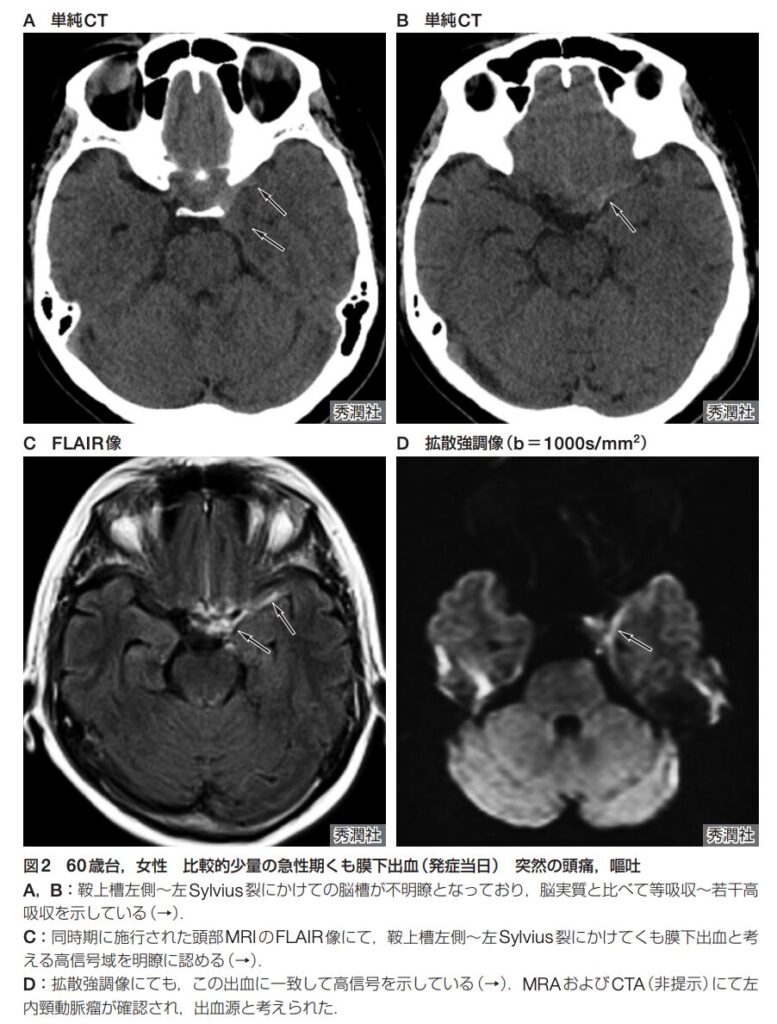

典型的なSAHの場合、頭部単純CTにおいて、脳の底部にある「鞍上槽」を中心として、前大脳縦裂、両側のシルビウス谷・裂、橋前槽、迂回槽へと血液由来の高吸収領域が広がり、いわゆる「ペンタゴン(五角形)」の形状を示します。このような典型例であれば診断は容易です。

少量の出血や、発症から時間が経過して血液の吸収値が低下している場合は、診断が困難になり見逃しの原因となります。 見逃しを防ぐためには、単に「白く光る高吸収域を探す」だけではなく、以下の視点で読影することが重要です。

- 左右差を比較する

- 脳槽や脳溝が、正常な脳脊髄液の吸収値(黒く抜ける状態)を示しているか?

- 脳槽や脳溝が不明瞭になっている部位はないか?

MRI

- 単純CTでSAHがはっきりしない場合や、発症から日数が経過している場合には、MRI(特にFLAIR像)が有用です。通常は髄液で黒く抜ける脳溝内に、FLAIR像で高〜等信号が見られればSAHの可能性が高いです(ただし、FLAIRでくも膜下腔が高信号を呈する病変・病態があります。詳しくは、「画像診断まとめ」様の「クモ膜下出血(SAH)のMRI画像診断(特にFLAIR) をご参照ください)。

時期別のMRIの感度

- 急性期(発症4〜5日まで):

- FLAIR像の感度は81〜100%。

- T2*強調像の感度は90.9〜94%。

- 急性期はFLAIR像が特に有用です。